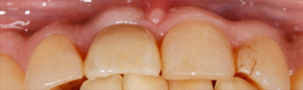

前から見ても歯が欠けてしまい、歯茎も赤く腫れてしまっているのが分かります。

下の口腔内写真は初診時と矯正治療+補綴治療後のものになります。

連結してあった前歯の被せ物(歯茎まで黒くなっている)も矯正後にきれいに治療することが出来ています。